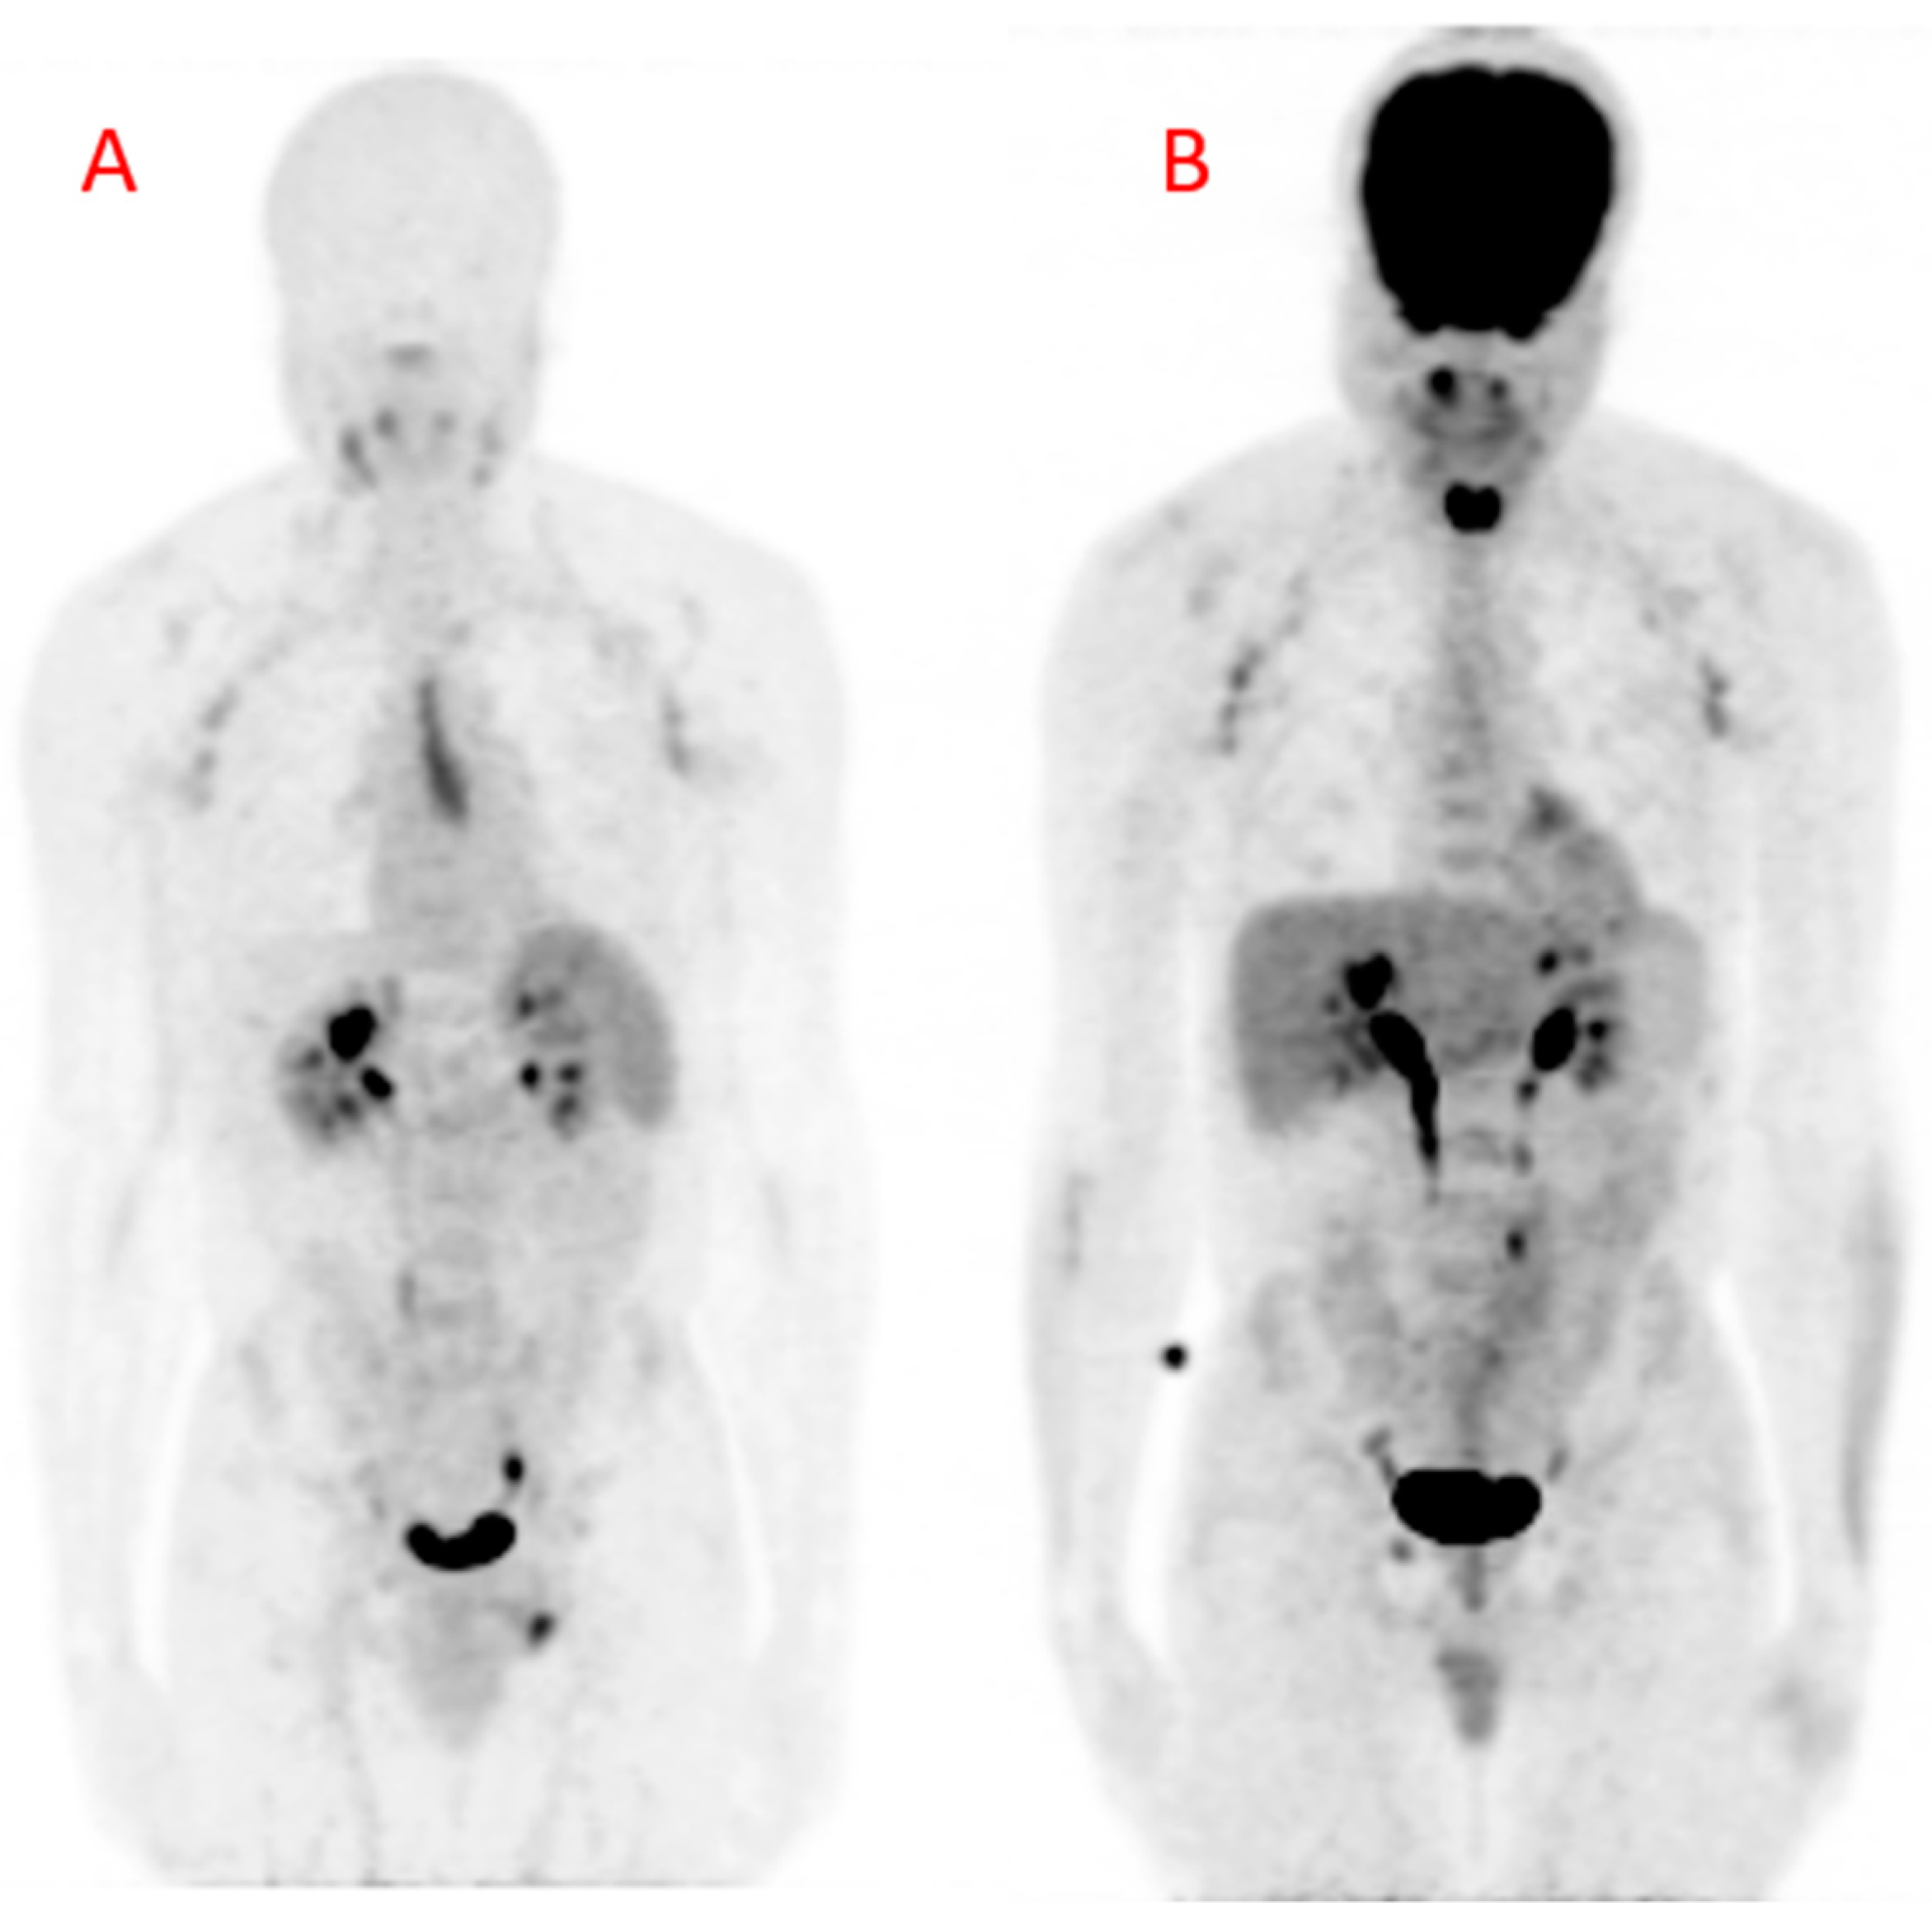

Figure 4. Maximum intensity projection (MIP) images obtained from (A) Gallium-68 pentixafor positron emission tomography ([68Ga]Ga-pentixafor PET) and (B) fluorine-18 fluorodeoxyglucose positron emission tomography (18[F]FDG PET) in a 42-year-old HIV-infected male. There are multiple mildly avid axillary lymphadenopathies and a urinary route of excretion of tracers on both images. The [68Ga]Ga-pentixafor PET image (A) shows physiologic tracer uptake in the spleen. The midline area of linear tracer uptake is localized to the thymus, likely related to inflammation associated with combination antiretroviral therapy (cART)-induced immune restoration. The [18F]FDG PET image (B) shows intense tracer uptake in the brain and the nasopharynx. There is also intense [18F]FDG in the muscles of phonation because the patient was talking during the period of uptake. This intense uptake can cause photon spill-over into the carotids during tracer uptake quantification. The patient arrived for the [18F]FDG PET/CT carrying a bag causing the diffuse [18F]FDG uptake in the lateral aspects of the forearms, more pronounced on the left. There is only minimal myocardial [18F]FDG uptake due to prolonged fasting in this patient.

Some important studies have shown the utility of [18F]FDG PET/CT in quantifying arterial inflammation in PLHIV [11,12]. [18F]FDG PET/CT studies have shown elevated arterial inflammation in PLHIV compared with age- and gender-matched controls [5,6]. In another study, [18F]FDG PET/CT was used to demonstrate residual arterial inflammation in patients who were treated with effective ART [13]. More recently, Hsue and colleagues demonstrated the utility of [18F]FDG PET/CT for treatment response assessment in HIV-infected people treated with canakinumab, an interleukin-1β inhibitor targeting arterial inflammation [14]. Some other studies have failed to show a significantly higher burden of arterial inflammation in PLHIV compared with non-HIV infected controls [15,16,17]. These contradictory findings may be related to the limitations associated with [18F]FDG PET/CT for arterial inflammation imaging [18]. Apart from the need for patients to fast and stop certain medications that can interfere with [18F]FDG biodistribution, there are important hurdles encountered when using [18F]FDG PET/CT for arterial inflammation quantification. The intense [18F]FDG accumulation in the myocardium and soft tissues of the neck precludes accurate arterial 18F-FDG uptake quantification in the coronary and carotid arteries, two of the most important arterial beds involved in ASCVD (Figure 4). During arterial [18F]FDG quantification for vascular inflammation imaging, the goal is to quantify [18F]FDG uptake by inflammatory cells. In ASCVD, [18F]FDG uptake in the vascular smooth muscle contributes significantly to the PET signal recorded during quantification [19].